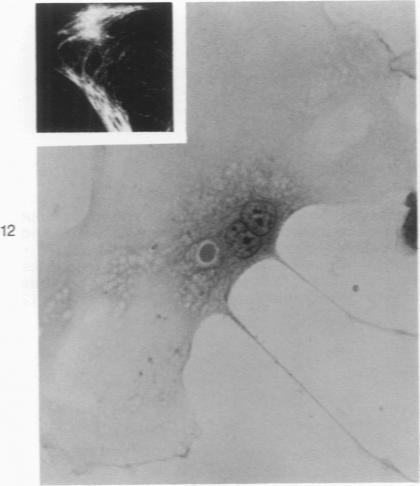

Astrocytic differentiation in monolayer cultures of ascitic embryoid bodies from the experimental teratoma OTT-6050 was studied by conventional light microscopy and by indirect immunofluorescence with antisera to glial fibrillary acidic (GFA) protein, a protein specific for astorcytes. Primitive neuroepithelial cells were identified in 24-hour cultures. Within 72 hours, two cell types diverged. One cell type, with a flattened epithelial morphology in early cultures, demonstrated delicate GFA protein-positive fibrils within 48 hours. In later cultures, this type progressively displayed more typical stellate astrocytic features, with denser, more compact GFA protein-positive fluorescence in the perinuclear cytoplasm and cell processes. As indicated by GFA protein expression, the appearance of astrocytes of typical morphology therefore was preceded by biochemical differentiation. The second cell type, interpreted as neuroblastic, failed to demonstrate GFA protein and had a small perikaryon with slender bipolar processes that were argyrophilic with Bodian's protargol in late cultures. Divergent neuroepithelial differentiation occurred within mitotically active cell populations and proceeded without apparent tissue relationships to other germ layer derivatives.

利用传统光学显微镜以及针对神经胶质纤维酸性(GFA)蛋白(一种星形胶质细胞特有的蛋白质)的抗血清进行间接免疫荧光,研究了来自实验性畸胎瘤OTT - 6050的腹水胚胎体单层培养物中的星形胶质细胞分化。在24小时的培养物中鉴定出原始神经上皮细胞。在72小时内,两种细胞类型出现分化。一种细胞类型在早期培养物中具有扁平的上皮形态,在48小时内显示出纤细的GFA蛋白阳性纤维。在后期培养物中,这种类型逐渐呈现出更典型的星形胶质细胞特征,核周细胞质和细胞突起中GFA蛋白阳性荧光更密集、更紧凑。因此,正如GFA蛋白表达所示,典型形态的星形胶质细胞的出现之前先有生化分化。第二种细胞类型被解释为成神经细胞,未显示GFA蛋白,并且在后期培养物中有一个小的核周体,带有细长的双极突起,用博迪安原银浸染法染色后呈嗜银性。不同的神经上皮分化发生在有丝分裂活跃的细胞群体中,并且在没有与其他胚层衍生物明显组织关系的情况下进行。